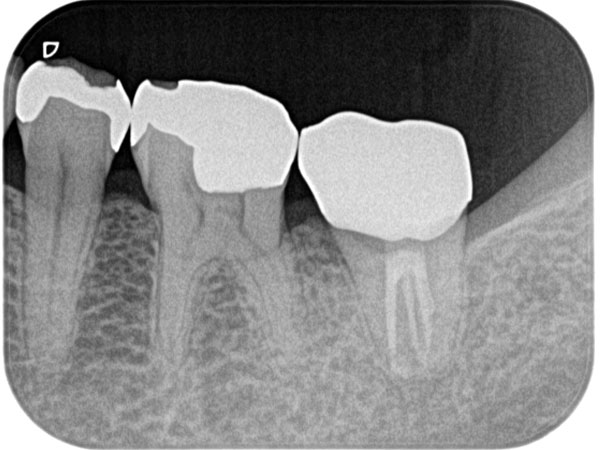

複雑な根管を治療するには、事前の画像診断で根管の形状を可視化することが重要です。多くの歯科医院では、画像診断に「2次元」のレントゲンが用いられますが、レントゲンでは初期の患部を見つけにくい上に、根管の複雑な形状をしっかり可視化するほどの力はありません。

そこで、当院では3次元で撮影ができる「CT」を利用します。CTはあごの骨の中を立体的に可視化するので、レントゲンには写らない患部の様子までがしっかりわかります。日本国内の歯科医院での、CTの普及率は5〜10%程度と言われています。